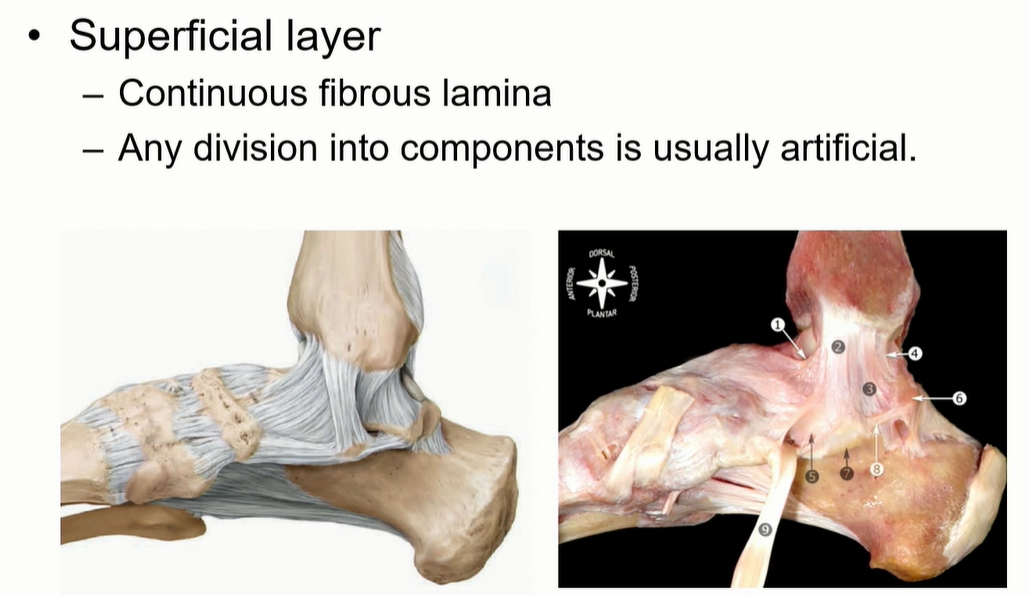

3. Deltoid ligament

Superficial은 사실상 연속적인 구조로 되어 있다. 구분은 인위적.